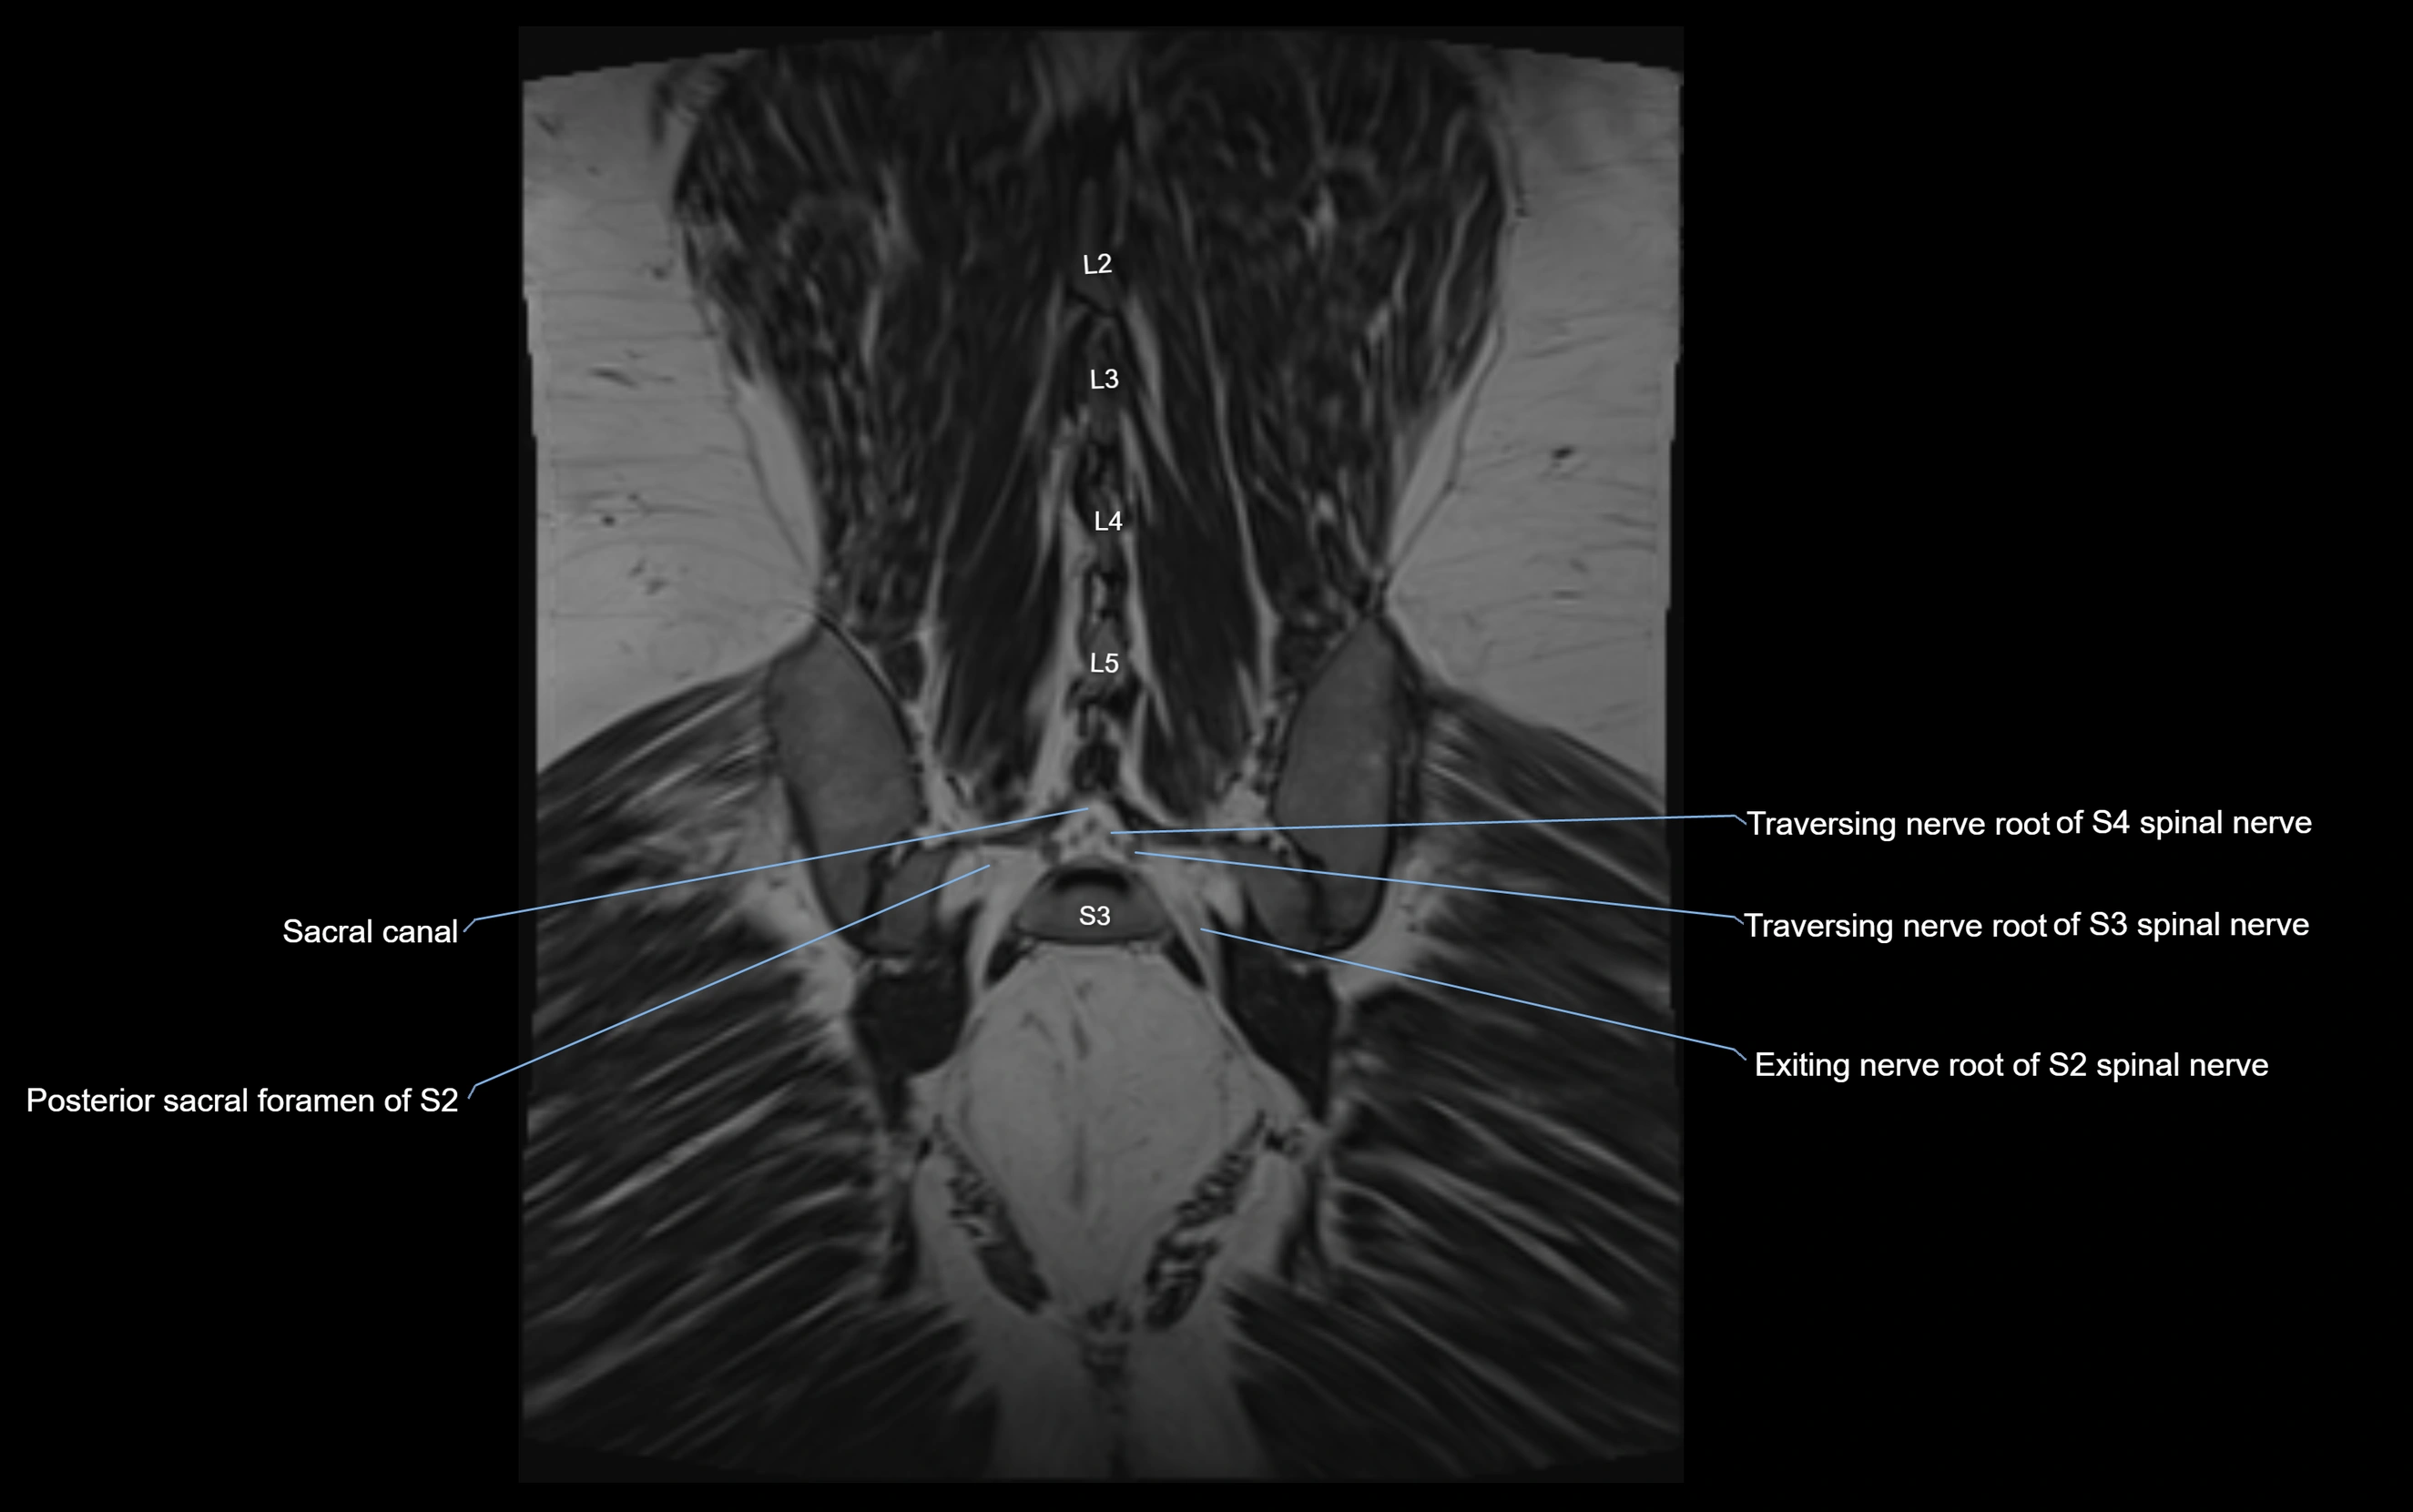

MRI Appearance

T1-weighted images:

• Nerve appears as a very thin low-to-intermediate signal intensity structure

• Surrounded by bright fat, aiding visualization

T2-weighted images:

• Nerve shows intermediate to mildly hyperintense signal compared to muscle

• Pathological involvement appears brighter

STIR (Short Tau Inversion Recovery):

• Normal nerve appears dark

• Inflamed or entrapped nerve appears bright hyperintense

T1 Fat-Sat Post-Contrast:

• Normal nerve enhances minimally

• Pathologic nerve (neuritis, entrapment, tumor infiltration) shows focal or diffuse enhancement

3D T2 SPACE / CISS:

• Nerve appears intermediate to mildly hyperintense compared to muscle

• Surrounded by bright fat or CSF, improving visualization

• Best sequence for mapping small pelvic nerves such as the anococcygeal